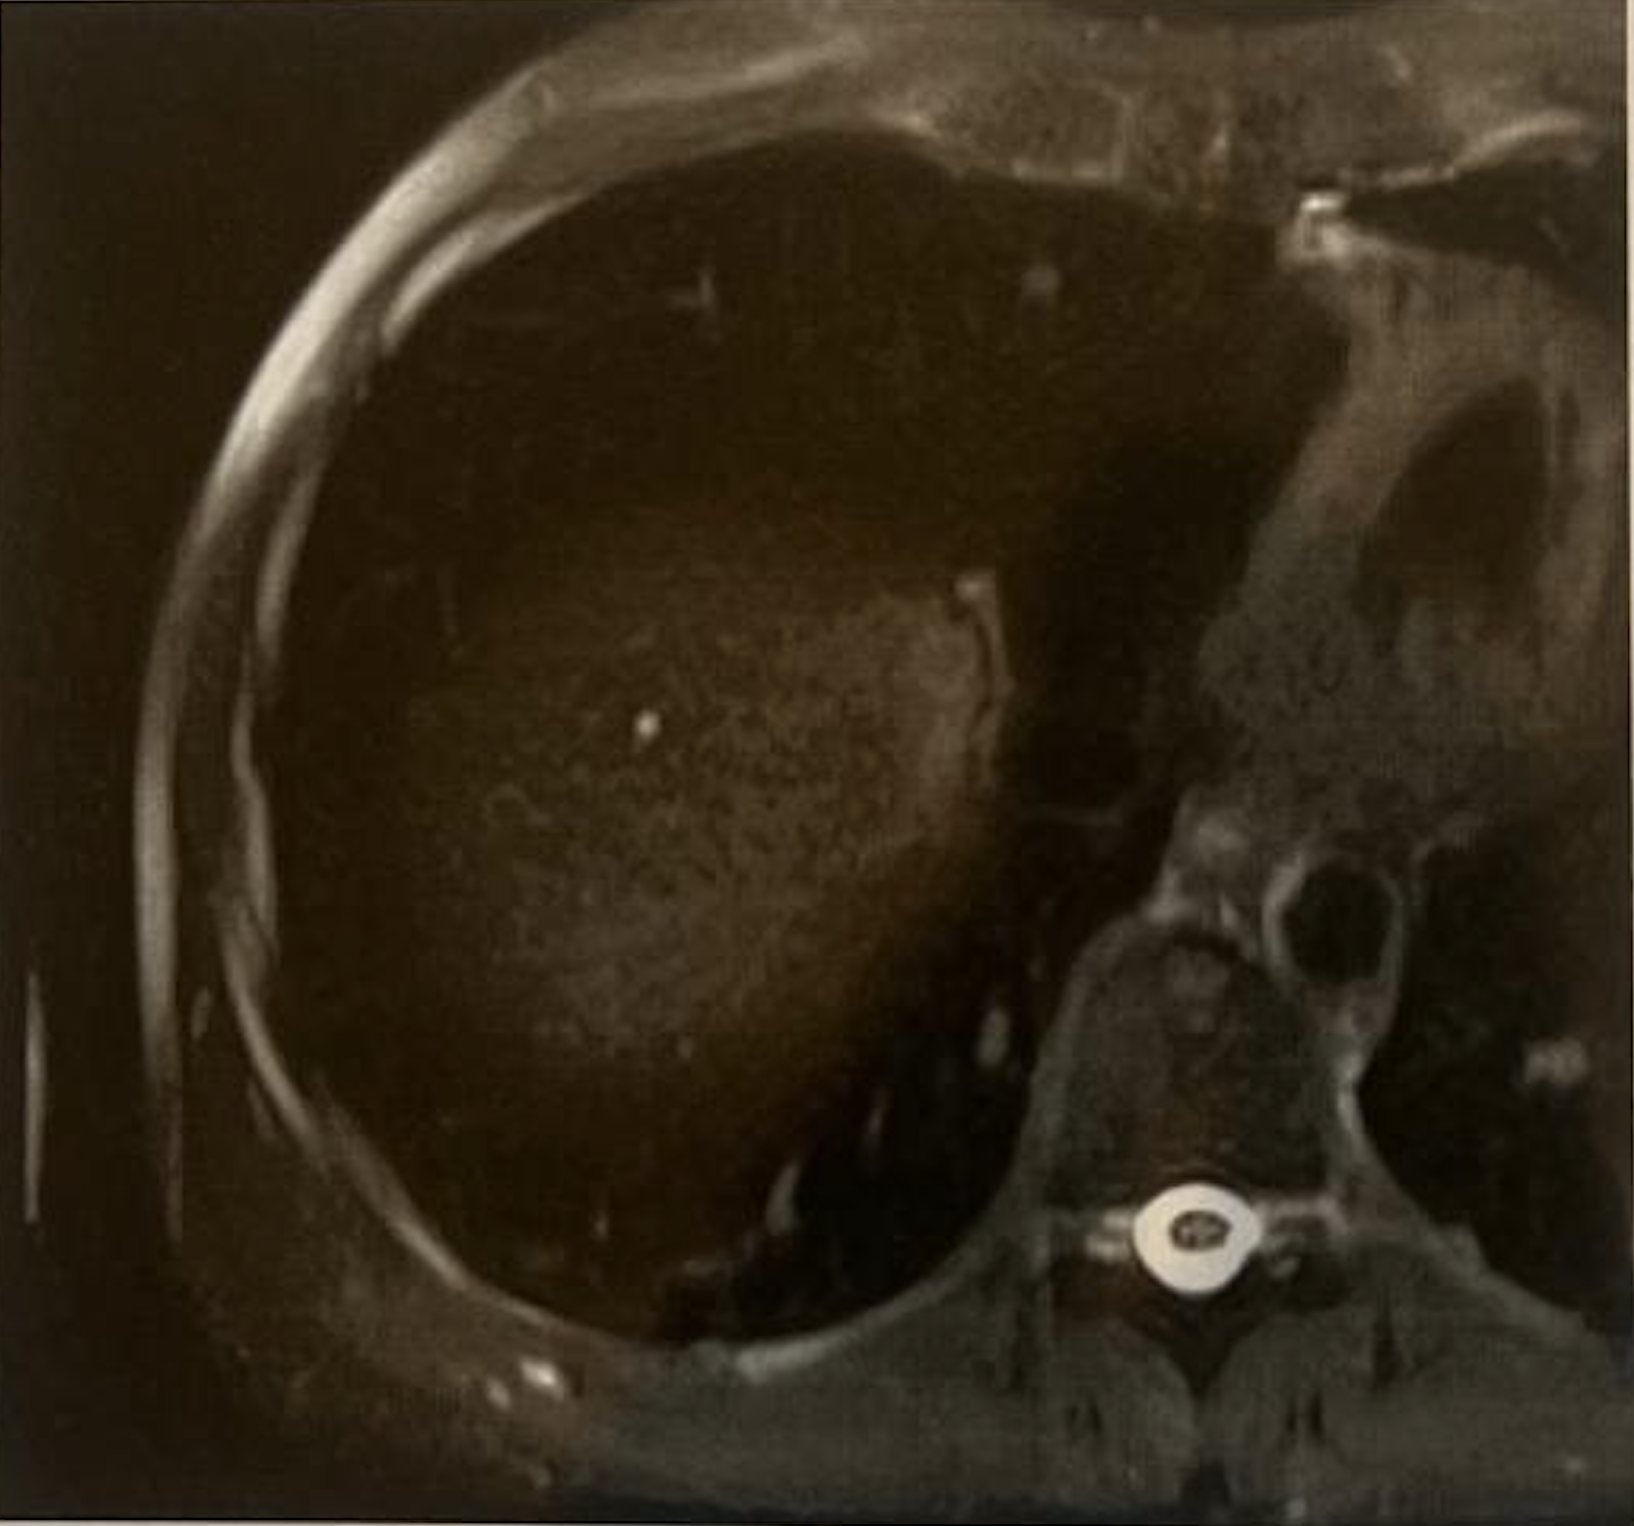

Despite his incredible fighting spirit and an extensive medical regimen, a CT scan in March 2025 brought challenging news. The scan revealed bilateral nodules scattered throughout his lungs and mildly enlarged lytic lesions in his bones. The disease was still progressing, but the patient and his family were not ready to stop looking for answers.

The dedication to this comprehensive, cross-border treatment plan truly paid off. Following the completion of his therapies, a recent CT scan brought a much-needed wave of relief. Compared with the difficult scans from earlier in the year, the new imaging showed a slight decrease in the size of the diffuse pulmonary nodules. The rest of his findings showed no significant changes, indicating that the aggressive progression of the disease had stabilized and that some of the lung lesions were actively shrinking.